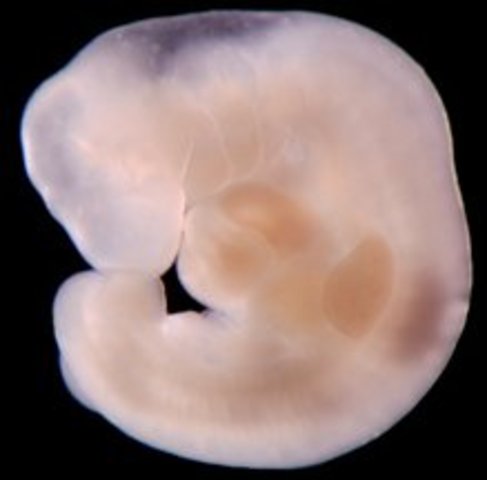

• week3

week3

1.The fertilized egg immediately begins dividing and floats down into the uterus

2.The sex of your baby is predetermined by the father’s sperm chromosomes

3., the cell starts to divide itself into 2 cells, then 4, 8 and so on rapidly